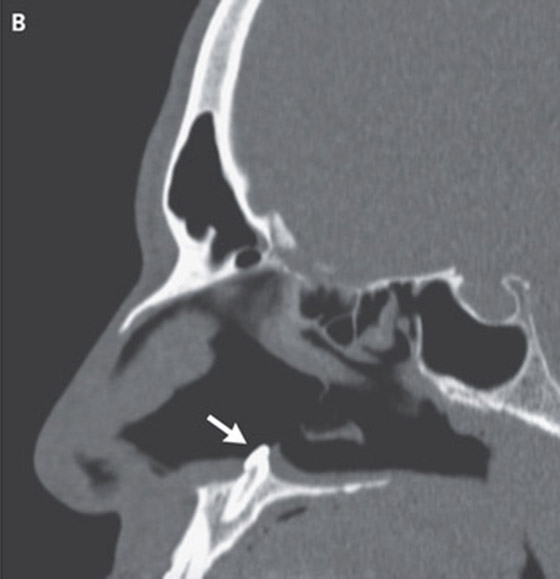

عندما بدأ المريض في الشكوى من ضيق التنفس، أجرى الفحوصات، ووجد الأطباء أنه يعاني من انحراف الحاجز الأنفي، بالإضافة إلى نمو يشبه العظم داخل الأنف. ظهرت هذه المضاعفات غريبة؛ لأن المريض لم يكن يعاني من أي تشوهات في الوجه. ومن أجل الوصول إلى أساس المشكلة، أجرى جراحو الفم والوجه والفكين فحص للأنف من خلال أداة تشبه الأنبوب، ليكتشف الجراحون وجود كتلة بيضاء تبدو كالسن تظهر من داخل فتحة الأنف اليمنى، ويبلغ طول هذا السن 15 مل.

تُعرف هذه الحالة بـ"الشذوذ الشمي"، وهي نادرة الحدوث، فوفقًا لدراسة في 2019، يعاني نسبة من 0.1% إلى 1% من الناس من هذه الحالة. ولا يزال غير واضح سبب نمو الأسنان داخل الفم، لكن يعتقد الأطباء أن السبب يتمثل في الالتهابات، والشفاة المشقوقة. ويرجع سبب إصابة ذلك المريض إلى أنه يعاني من انشقاق في سقف الأنف منذ الولادة.